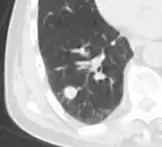

Calcifications and popcorn-like appearance, conferring a diagnosis of hamartoma.[9]

• In case of calcifications, a popcorn-like appearance indicates a hamartoma, which is benign.[3]